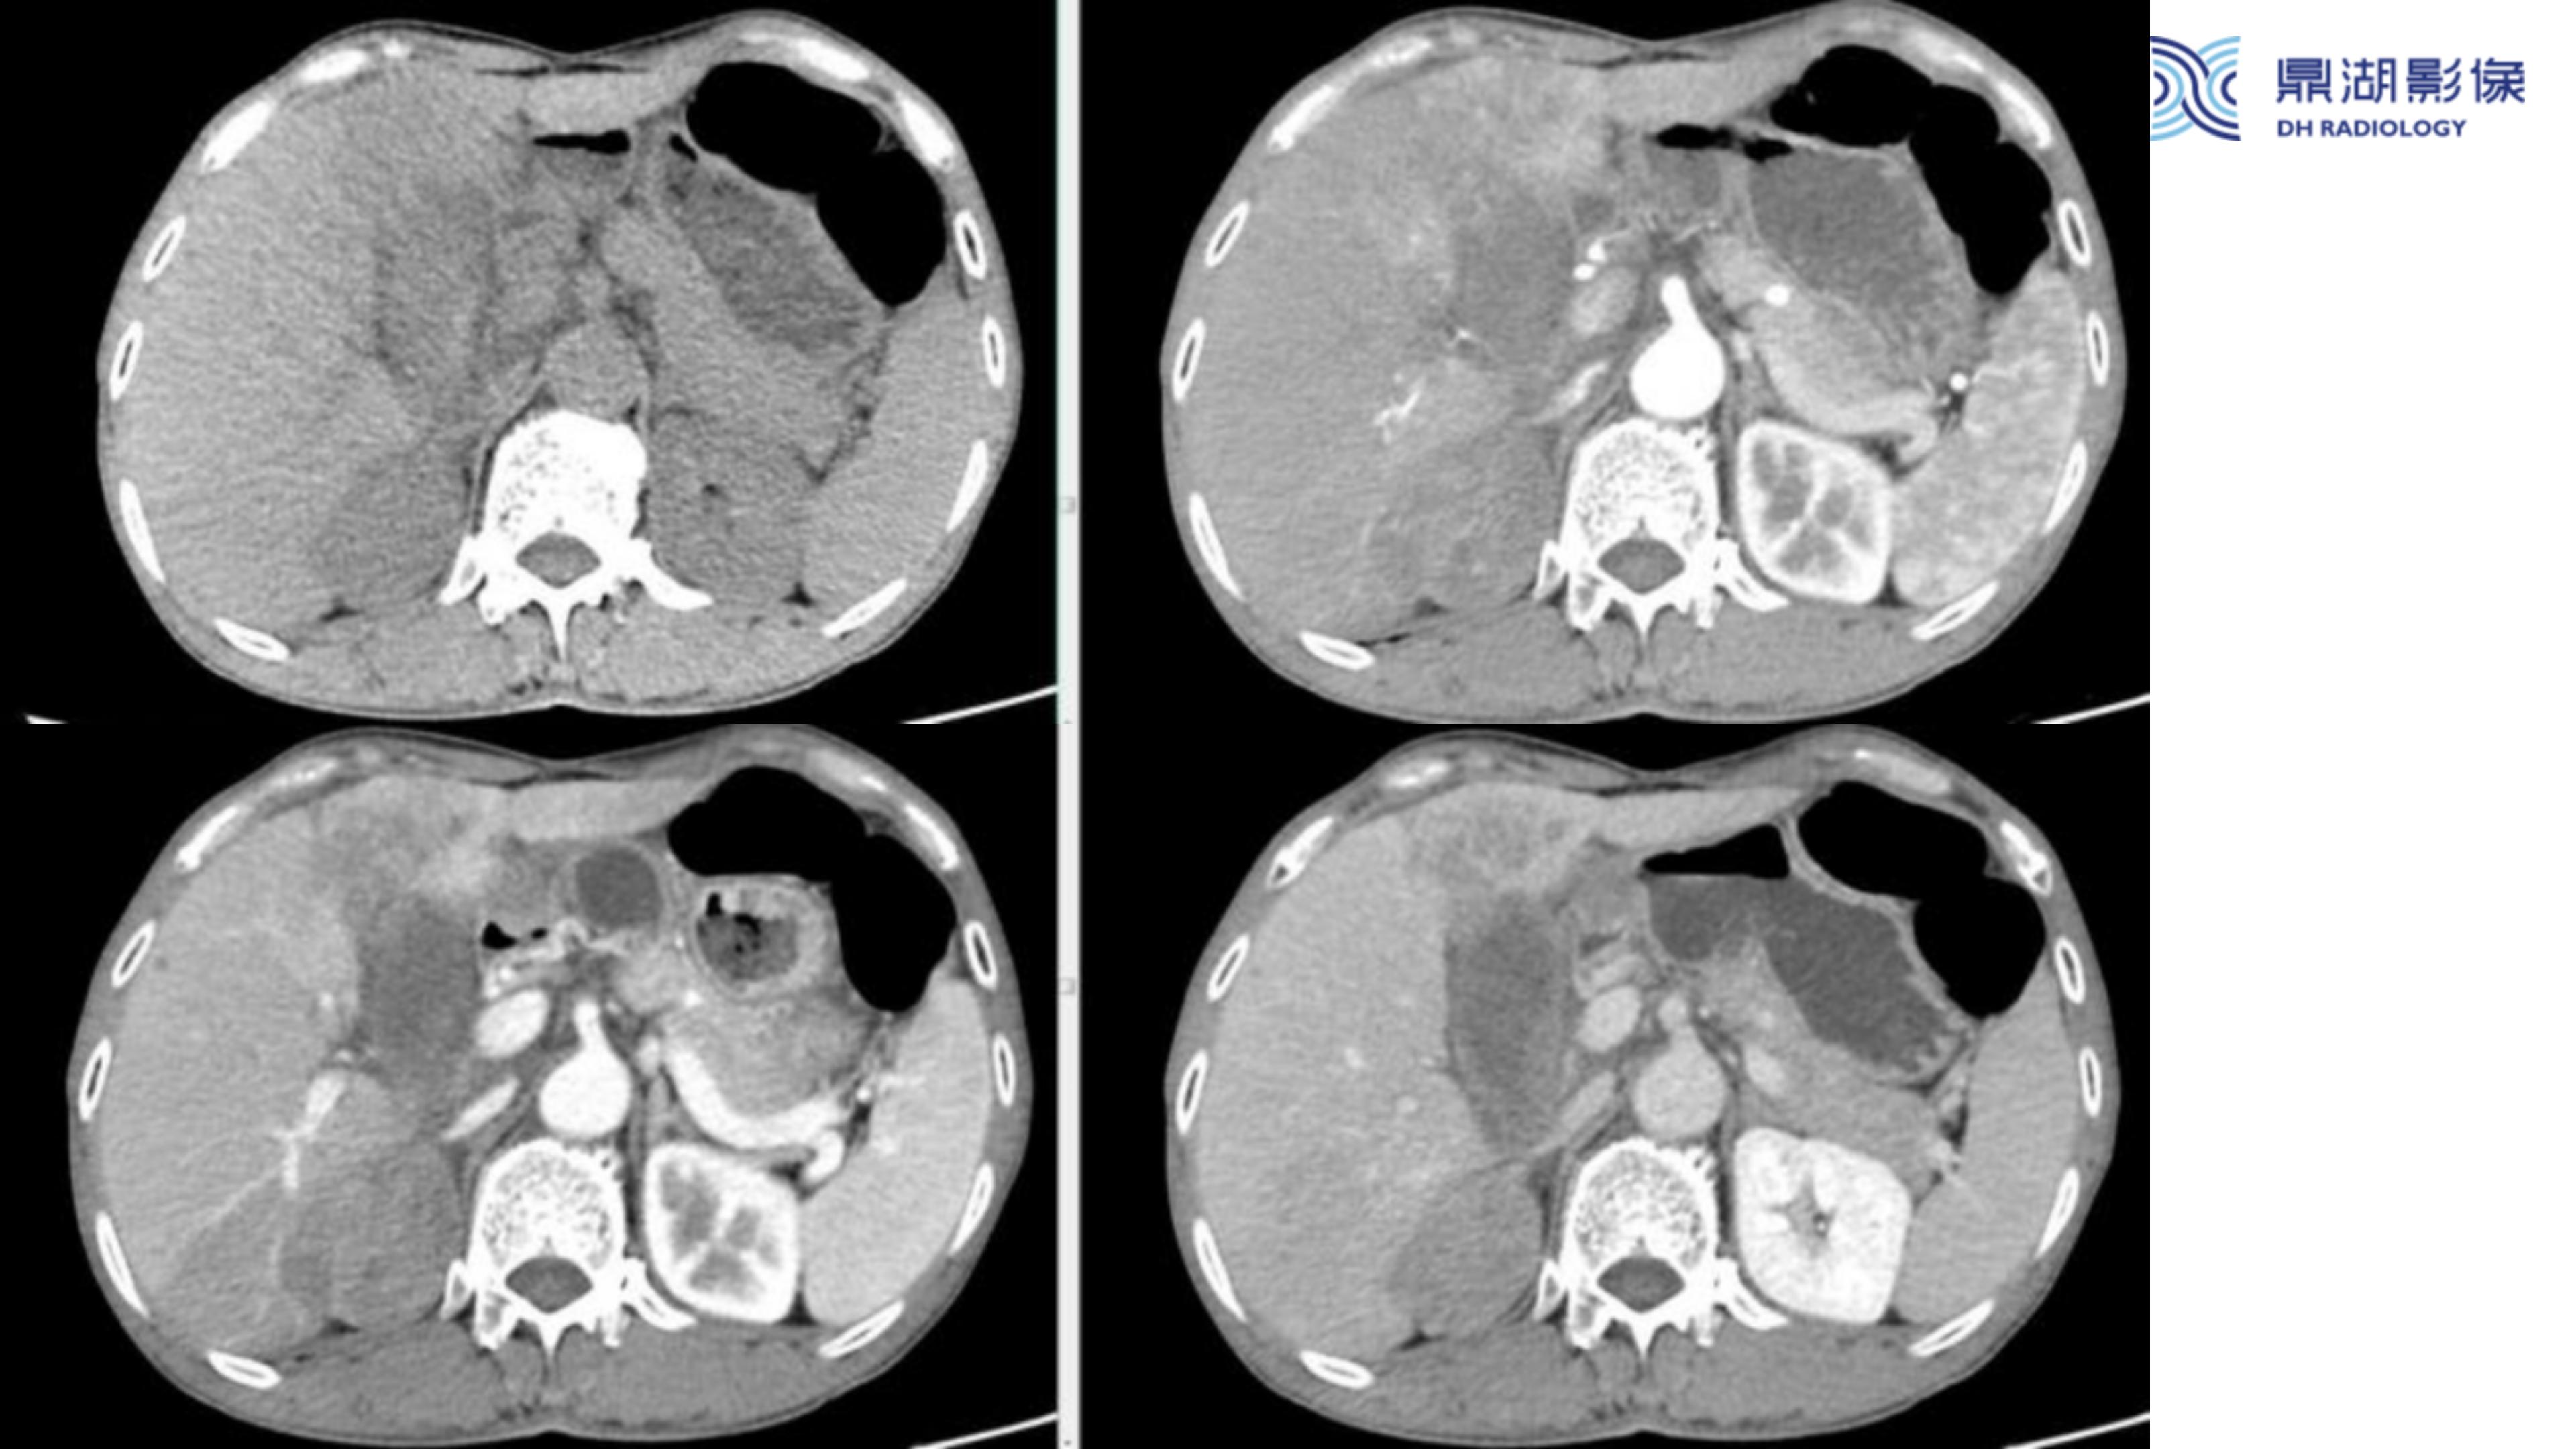

胆囊癌-鼎湖社群读片病例